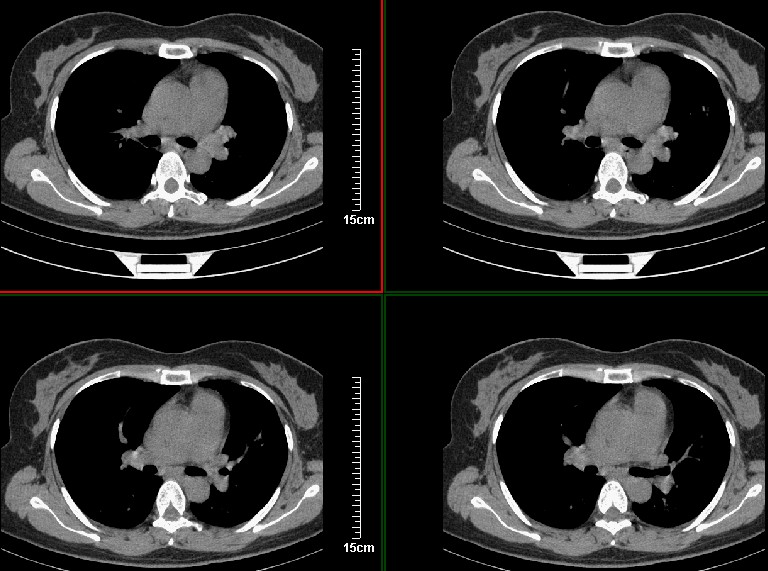

一周之后 复查结果 5mm扫描 40多岁 我们医院的护士

病灶分明小多多了

好像和8248是同一个人的病例吧??呵呵,8248大家都认为是感染,现在又都认为是肺癌,图像小了一点,诊断结果就差别这么大。